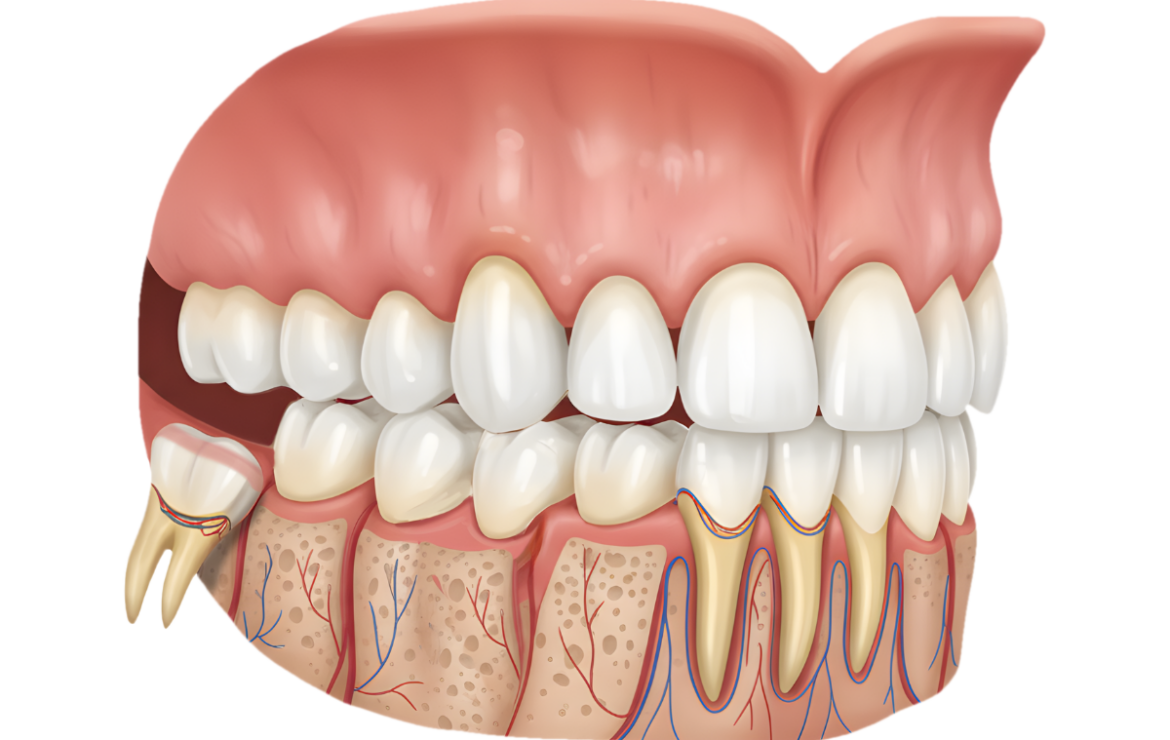

L’estrazione del dente del giudizio è un intervento odontoiatrico frequente, che viene eseguito soprattutto in caso di denti problematici che causano infiammazione o dolore. Nei giorni successivi all’intervento, una corretta fase di post-trattamento è particolarmente importante, poiché influisce in modo significativo sulla rapidità e sulla regolarità della guarigione. Con la giusta attenzione nei primi giorni, i fastidi possono essere notevolmente ridotti.

🦷dolore lieve o moderato nella zona dell’intervento,

🦷gonfiore nella zona del viso o delle gengive,

🦷lieve sanguinamento nelle prime ore,

🦷sensazione di tensione nella mandibola.